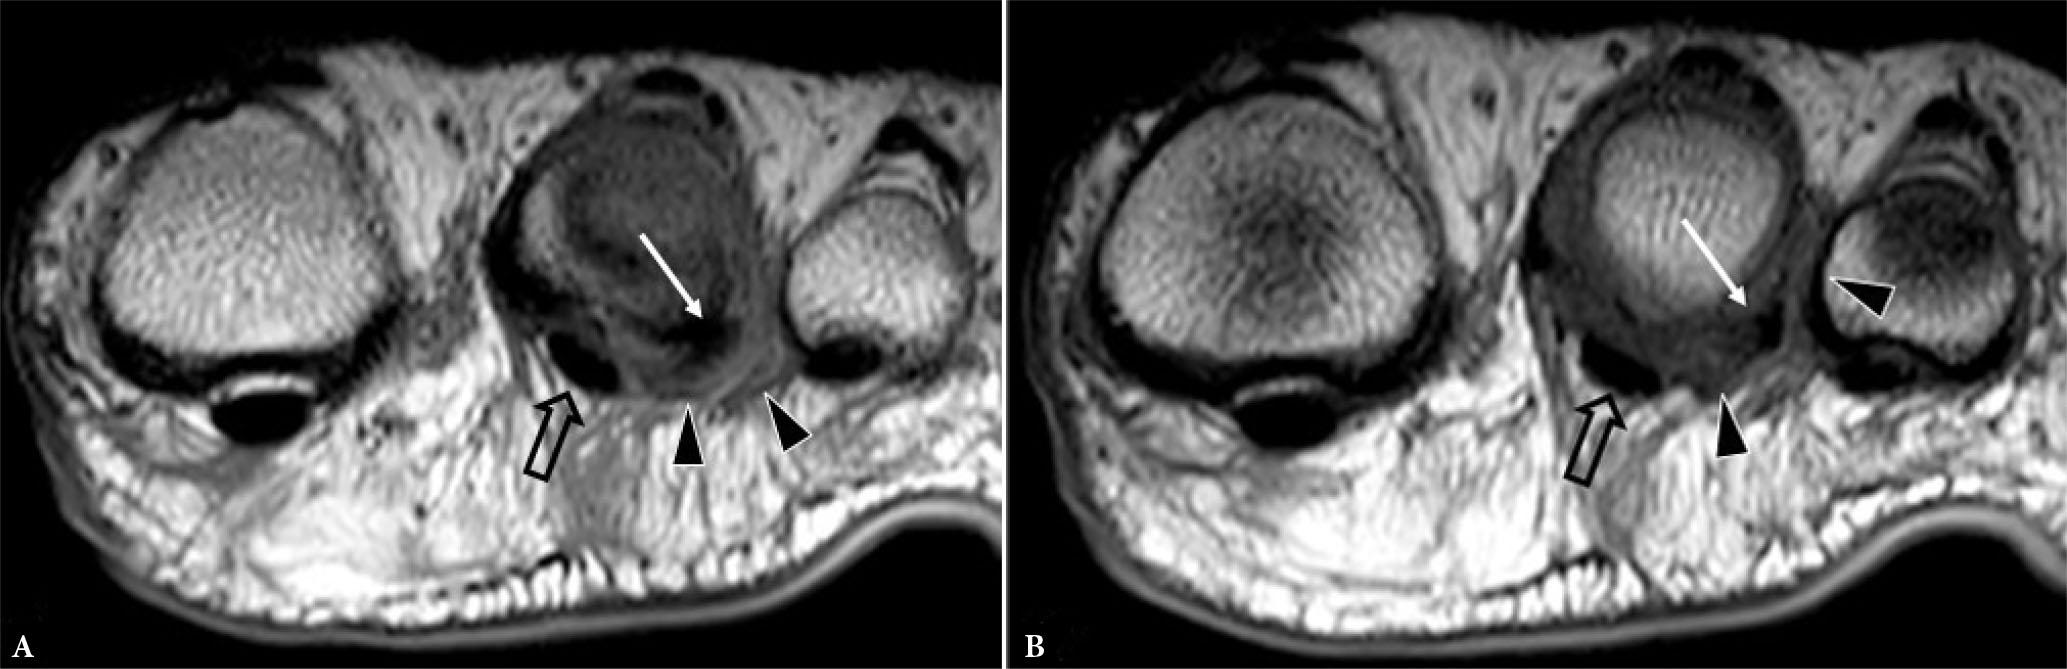

Fig. 14.

31–year-old female professional basketball player with forefoot pain. A, B. Consecutive longitudinal greyscale US images shows moderately thickened plantar plate (arrowheads) of the 2nd MTP joint with a long intrasubstance tear (short arrows). C. Transverse greyscale US image shows moderate pericapsular fibrosis (long arrow) inferolateral to the 2nd MTP joint. D. Longitudinal greyscale US image of the asymptomatic normal contralateral 2nd MTP joint plantar plate for comparison. (images courtesy of Dr James Linklater)

Fig. 15.

Same patient as previous figure. Sagittal A. proton density (PD) and B. T2W FS images shows a moderately thickened plantar plate (arrowheads) of 2nd MTP joint with intrasubstance tear (short arrow). C, D. Coronal T2W fat-suppressed MR images shows moderate-severity reactive pericapsular fibrosis (long arrow) inferolateral to the 2nd MTP joint with moderate pericapsular inflammation (open arrowheads). The plantar plate tear was confirmed and treated surgically, with subsequent return to sports (images courtesy of Dr James Linklater)

The 2nd, followed by the 3rd, MTP joint plantar plates are the most frequently injured(12). Plantar plate tears typically occur at the junction between the plantar plate and the accessory collateral ligament close to the phalangeal attachment, most commonly at the inferolateral aspect of the joint (Fig. 13). On US, most plantar plate tears are seen as discrete partial or full thickness hypoechoic defects in the plate substance(13,14). Flattening or attenuation may occur with plantar plate degeneration. When the plantar plate is completely torn, the flexor digitorum tendon may directly contact the metatarsal head(13,14). In the chronic setting, reactive pericapsular fibrosis can be seen as a non-compressible hypoechoic cuff of tissue abutting the plantar and inferolateral (or inferomedial) aspects of the MTP joint(13,14). US should be performed in both longitudinal and transverse planes, scanning the plantar aspect of the MTP joint slowly from lateral to medial and from distal to proximal, with angling of the transducer to avoid anisotropy. Most injuries occur at the distal attachment of the plate. Longitudinal US is best to detect and characterize tears while transverse US is useful to delineate the eccentric location of pericapsular fibrosis and to exclude subluxation of the flexor digitorum tendon. Longitudinal US during toe dorsiflexion can improve tear detection and appreciation of MTP joint subluxation(14).

For MR imaging, T1-weighted (T1W) coronal images are usually the most helpful as routine sagittal forefoot images do not always image the plantar plate in a true sagittal plane(12) (Fig. 15). Performing MRI in the prone position, with the foot in plantarflexion, results in less magic angle artifact and less movement artefact potentially facilitating assessment of the plantar plate(11). Prone positioning also leads to slight plantar shift of the interdigital soft tissues improving assessment of Morton’s neuroma(15). Dynamic US assessment during MTP joint dorsiflexion or during dorsal drawer (Lachman) testing can help assessment of plantar plate integrity and MTP joint stability. Compared with surgical findings, the pooled sensitivity (93%) of US for detecting plantar plate tears is comparable to that of MRI (89–95%), though MRI has a higher specificity (54–83%) than US (33–52%)(16). A negative US examination makes plantar plate injury very unlikely. If US is positive or equivocal, MRI can provide more specificity as to the nature of the injury and yield a more global assessment of the MTP joint(17).